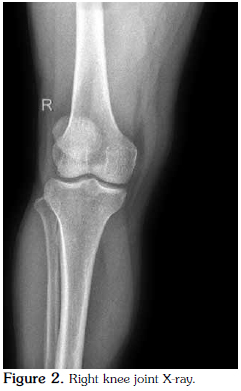

The bilateral knee radiographs of the patient were normal (Figure 2), but those of the feet revealed osteodegenerative changes (Figure 3) and bilateral heel spurs (Figure 4).